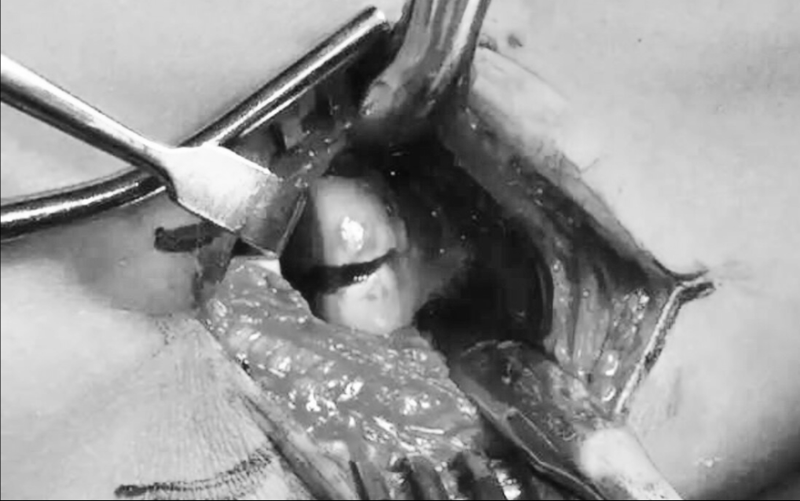

①EDC入路:2型3型桡骨头赤道线前半球骨折,选择EDC劈开入路(Extensor Digitorum Comunis入路)指总伸肌劈开入路更为靠前,可以更容易的显露桡骨头赤道前侧,方便手术时固定。

图3 EDC入路指总伸肌劈开入路DC入路中,确定DC肌后,自其在肱骨外上的起点正中间切开,向远端题伸至肱桡关节以远25mm处,在外侧切带复合体(起于肱骨止于尺骨),在其尺骨附着点的前方切开外侧关节囊

图4 EDC入路延长的DC入路的创伤较小,因为它保留了尺侧腕伸肌的起点和指总伸肌起点的后半部分.EDC劈开入路可以提供更大、更可靠的烧骨头前部骨折的显露,可以减少医源性出损伤尺外侧鼎副韧带并引起后外侧旋转不稳定的风险

图8 EDC入路切口